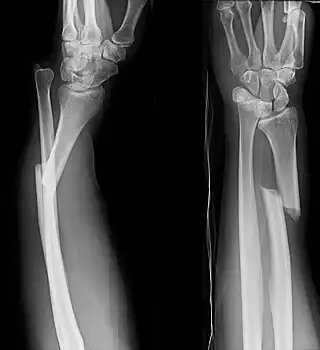

![]() Radiografías anteroposterior y lateral de un antebrazo con la fractura de Galeazzi. | ||

La fractura de Galeazzi consiste en la fractura de la diáfisis radial con luxación del cúbito a nivel de la articulación radiocubital distal. La lesión produce una disrupción a nivel de la articulación de la muñeca